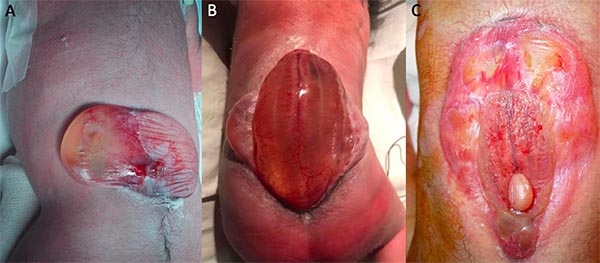

La extensión del disrafismo al nacimiento puede predecir la severidad del daño neurológico que presenta el paciente (fig. 6).

Figura 6: Fotografías de mielomeningoceles. A: disrrafismo que genera exposición de un segmento medular extenso. B: disrrafismo de extensión moderada. C: disrrafismo con mínima exposición de tejido neural.